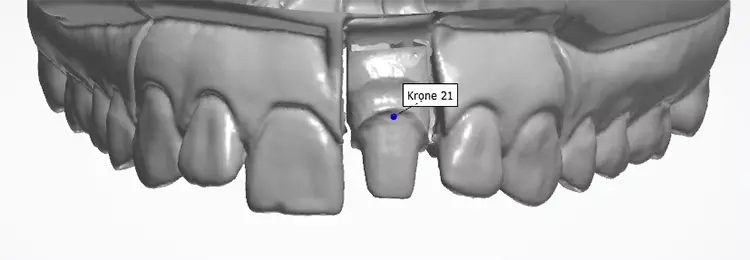

Auf den vorab hergestellten Situationsmodellen wurde für die provisorische Versorgung eine Tiefziehfolie für den Oberkiefer hergestellt. Es erfolgte die schonende Abnahme der Einzelzahnrestauration und die Entfernung des Befestigungsmaterials.

Die vorgefundene Präparation konnte im labialen Bereich in 3 Ebenen anatomisch reduziert und optimiert werden. Bei der Platzierung des zirkulären Präparationsrandes war die „biologische Breite“ nicht berücksichtigt worden und der Kronenrand lag deutlich subgingival.

Die Gingiva wurde mithilfe eines Retraktionsfadens vorsichtig verdrängt und die zirkuläre Präparation mit einer ausgeprägten Hohlkehle klar definiert. Beim Langzeitprovisorium, welches man in der Praxis herstellte, wurden sämtliche ästhetischen und funktionellen Parameter berücksichtigt und die „äußere Hülle“ der definitiven Krone festgelegt.

Gleichzeitig wurde mit den initial angefertigten Silikonschlüsseln die anatomische Reduktion des Zahnes 21 visualisiert und die labiale Reduktion in 3 Ebenen bewertet. Die Zielfarbe der Restauration und die Stumpffarbe wurden vor der Abformung für das zahntechnische Labor bestimmt und mit Fotos dokumentiert. Nach Darstellung des Präparationsrandes mittels Retraktionsfaden und Teflonband erfolgte eine klassische Abformung mithilfe eines individuellen Löffels und eines Polyethermaterials (Abb. 11–20).